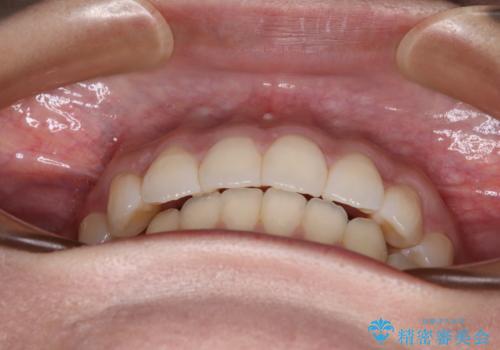

前歯のデコボコを解消 インビザラインの矯正治療

- 前歯のデコボコを治したいとのことで来院された患者様です。

上下顎ともに歯列全体の後方移動とIPR(歯と歯の間を削る)によってデコボコが解消するように設計し、インビザラインにより治療を行うこととしました。